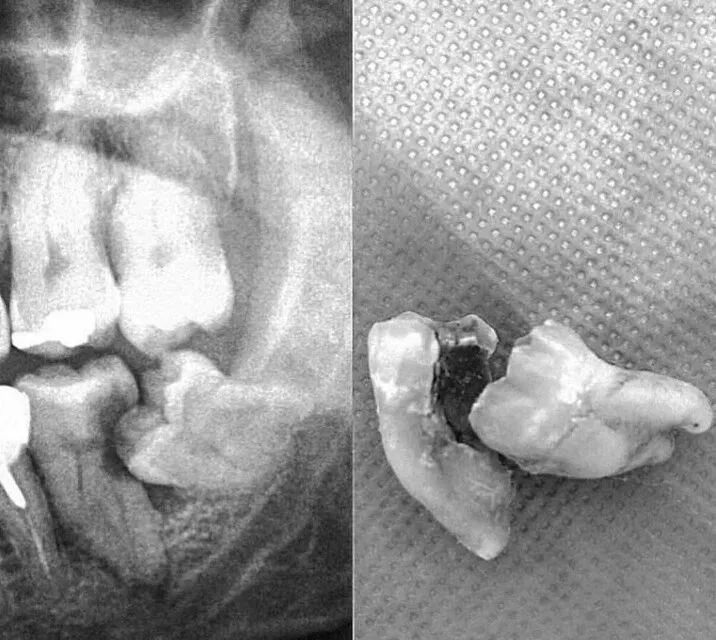

但是,如果阻生智齿如果长成下图这样子,虽然你的智齿不痛,但是位置不正,虽然它自身没坏,但它把前面的牙齿破坏出一个大洞,好好的大牙就被顶坏了,龋齿了,然后拖着没处理,导致牙髓也感染了,到时候两颗就要一起拔了。

▲阻生智齿

阻生智齿必须拔除,并且拔除的难度远远大于一般智齿。